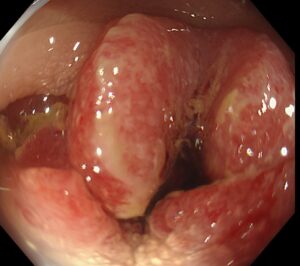

1ヶ月前から便秘と下痢を繰り返し出現した進行大腸癌の一例

2026-03-08